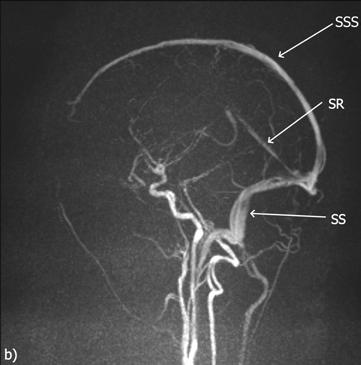

Obr. 2.28 A + B Žilní splavy – MR angiografie (snímek z vyšetření Jakub Čivrný)

MR venografie, metoda time-of-flight (TOF), MIP rekonstrukce maximum intensity projection, axiální řez (a) a sagitální řez (b).

SSS – sinus sagittalis superior, SR – sinus rectus, SS – sinus sigmoideus, ST – sinus transversus